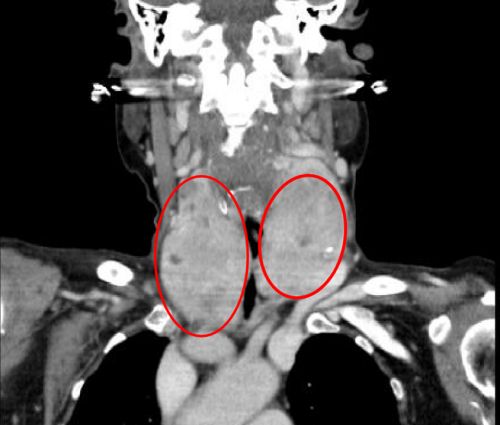

ct显示:左侧甲状腺肿瘤有成人拳头大小。

ct显示:巨大的右侧甲状腺肿瘤从颈部延伸至胸腔。

双侧巨大甲状腺肿瘤将气道挤压成一条细缝。

完善相关检查发现,老人左侧颈部有一个成人拳头大小的肿块,右侧颈部肿块更大、且向胸腔内生长。耳鼻咽喉头颈外科、呼吸内科、心血管内科、心胸外科、放射科、麻醉科、手术室等多学科专家讨论后一致认为,患者高龄且有冠心病等基础疾病,而且肿瘤巨大,手术难度和风险都很大。

据主刀的肖旭平主任医师介绍,两个巨大的肿块“左右夹击”,导致颈段气管被压成了一条细缝,造成呼吸困难,术中极易出现窒息,给麻醉插管带来很大的风险。手术团队在精细操作的同时,巧妙利用肌肉间隙入路,既顺利切除巨大肿瘤,又减轻了创伤、缩短住院时间、有助于快速康复。